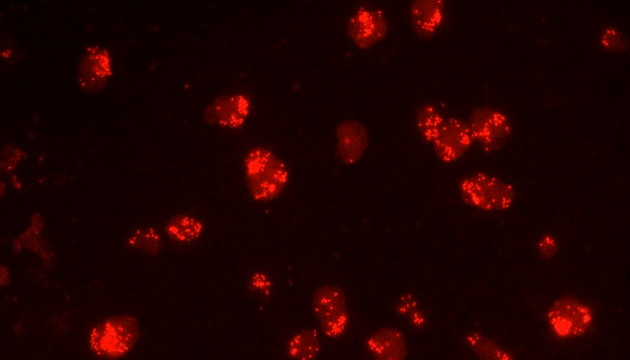

荧光原位杂交(Fluorescence In Situ Hybridization,FISH)是临床病理检测中广泛运用的一种分子细胞遗传学诊断技术,其原理是用荧光染料直接或间接标记的DNA核酸探针与待测样本中的DNA核酸序列按照碱基互补配对的原则进行杂交,然后通过荧光显微镜观察荧光信号位置、数量等来判断待测序列的缺失、扩增及易位等情况。其高分辨率、直接反映异常细胞比例、快速简便的特点,使其成为临床检测、预后评估及用药指导的重要工具。

FISH技术面临荧光弱、背景噪声、多通道叠加等难点。为了保障荧光信号强度,一般需要用到研究级荧光显微镜,半复消色差或以上的物镜,以及高功率的LED荧光光源或汞灯光源;为了去除背景噪声,一般需要搭配高截止深度的滤光片和高灵敏度相机;多通道叠加时要提取红绿信号点,然后放到蓝色DAPI信号上,处理需要相当的技巧。